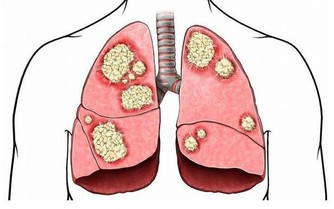

直腸癌跟肺癌的症狀一樣,在早期的時候經常被忽視。

下面帶你去瞭解一下直腸癌的症狀有哪些?